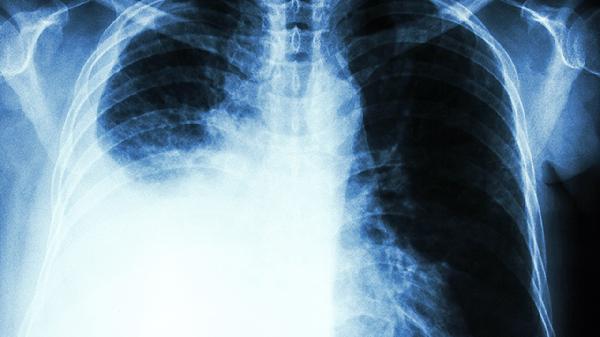

为什么肺癌去世的老人越来越多?医生指出:3件事要注意,别不听劝

最近总能在小区里听到救护车的鸣笛声,细问之下多是老人肺部出了问题。现代医学数据显示,呼吸系统疾病确实在老年群体中呈现上升趋势。这背后究竟藏着哪些我们忽视的生活细节?

超过两周的干咳、痰中带血丝、声音嘶哑,这些症状常被误认为是"老慢支"或"咽炎"。建议每年做一次低剂量螺旋CT检查,辐射量相当于坐两次飞机。